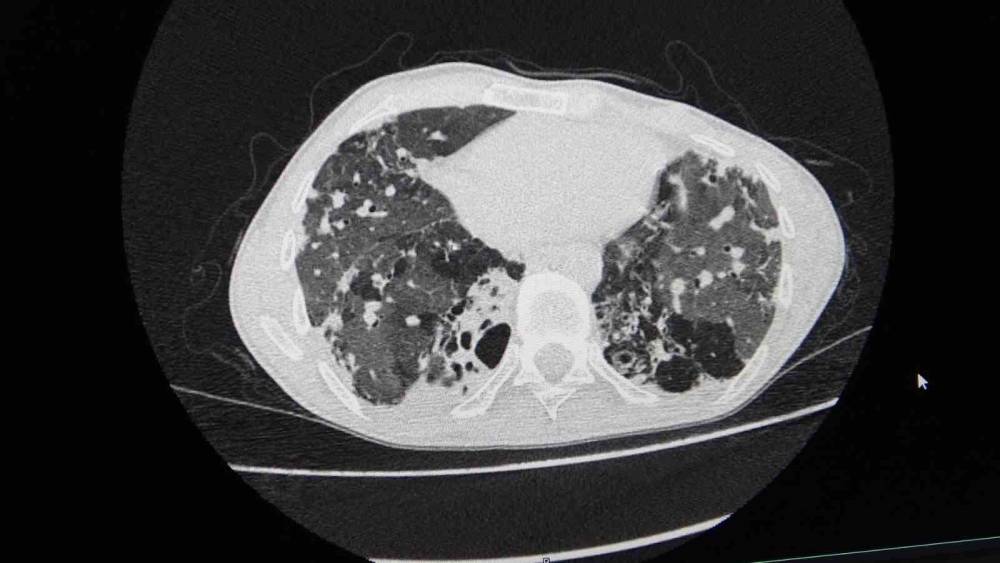

"Hastamızın yaşaması için tek çare nakildi"

Göğüs Cerrahisi Uzmanı Prof. Dr. Ahmet Erdal Taşçı, akciğer nakli bekleyen hastanın yıllardır bronşektazi hastalığıyla mücadele ettiğini belirterek, "Hastamızın yaşaması için tek çare nakildi. Nakil başarılı geçti. Bu operasyon, bizim ekibimiz için teknik anlamda standart bir akciğer nakliydi. Ancak dikkat çeken nokta, aynı anda hastanemizde bir karaciğer nakli operasyonunun da gerçekleştirilmiş olmasıydı. Aynı bağışçının organları, iki ayrı hastaya; biri akciğer, diğeri karaciğer olarak nakledildi. Bu vesileyle bağışçımıza Allah’tan rahmet, yakınlarına da sabır diliyoruz. Böylesine acılı bir anda başkasının hayatına dokunabilmek, örnek bir davranış" dedi.

"Yeni akciğerleriyle nefes alacak"

"Organ nakli, bir ülkenin sağlık sisteminin ne kadar gelişmiş olduğunu gösteren önemli bir göstergedir." diyen Taşçı, "Ameliyatı gerçekleştirilen hastamız, yoğun bakımda uyanık ve solunum desteğiyle izleniyor. Kısa sürede yeni akciğerleriyle nefes alması bekleniyor" diye konuştu. Taşçı, "Türkiye’de özellikle kadavra donör organ bağışlarının artması büyük önem taşıyor. Herkesin bir gün kendisinin veya sevdiklerinin de bu ihtiyaca düşebileceğini düşünerek, organ bağışı konusunda daha duyarlı ve bilinçli hareket etmesi gerekiyor. Ülkemizde Sağlık Bakanlığı’nın bu alandaki organizasyonu ve altyapısı gerçekten çok iyi seviyede. Bu anlamda emeği geçen herkese teşekkür ediyoruz" ifadelerini kullandı.